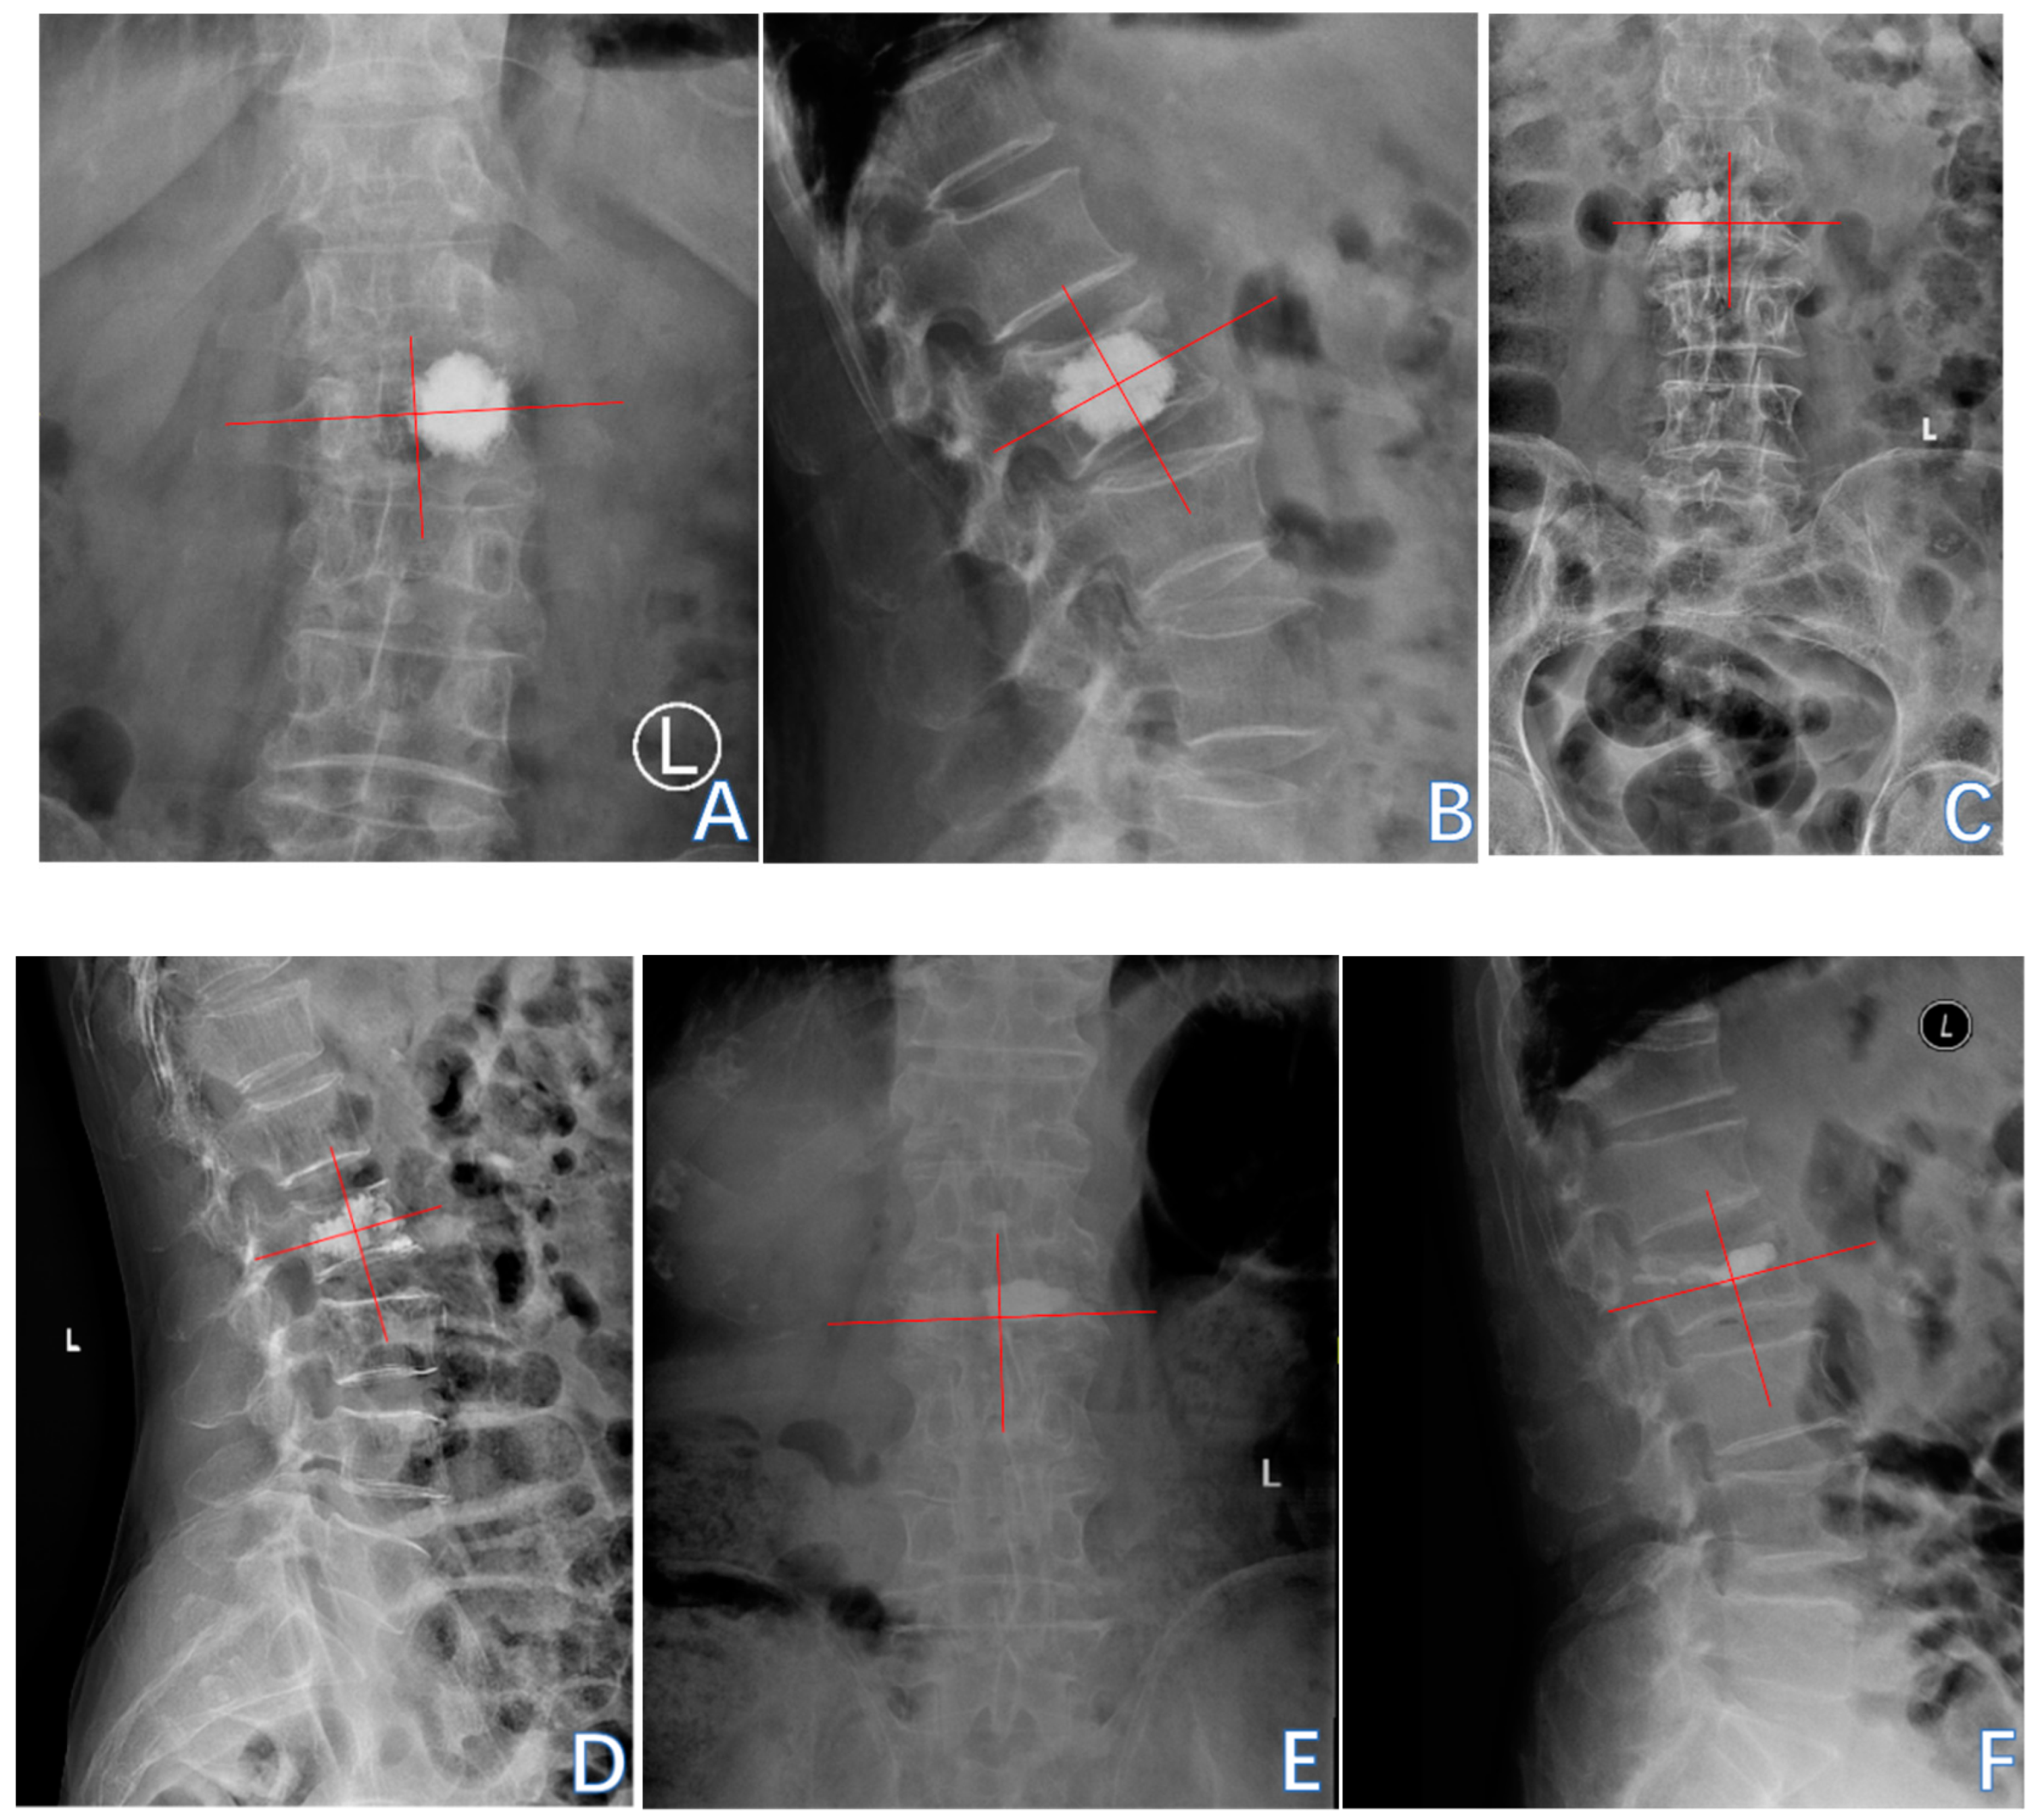

3.2. Augmented Vertebral Refractures

3.2.1. Univariate Analysis

3.2.3. Receiver Operating Characteristic (ROC) Curve